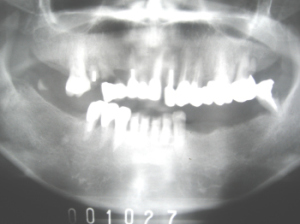

| 前歯が抜けてきた(動揺)として当院に来院 2000年10月27日 =解説= 奥歯に歯がないため、前歯に負担がかかって前歯が動揺 |

| 2000年11月18日に右の上下にインプラント植立。 同時に金属製の前歯を除去して、右奥歯と前歯にプラスチック製の歯(仮歯)を作る。 |

| 2日後、左奥歯にインプラント植立 これで両方の奥歯が噛めるようになりました。 |

| 後日残りの部分にインプラント植立。 これですべての歯が揃いました。 この状態で、骨が固まるまでプラスチックの歯(仮歯)で3〜6か月待ちます。 (抜歯してすぐ植立した前歯のインプラントが一部感染したので、打ち直しをしています。) |

| 6年後の2007年に来院時の写真。 右下の自分の歯がとれたと来院。 インプラント部分で何でも噛めると言っていました。インプラントは極めて良好。 |